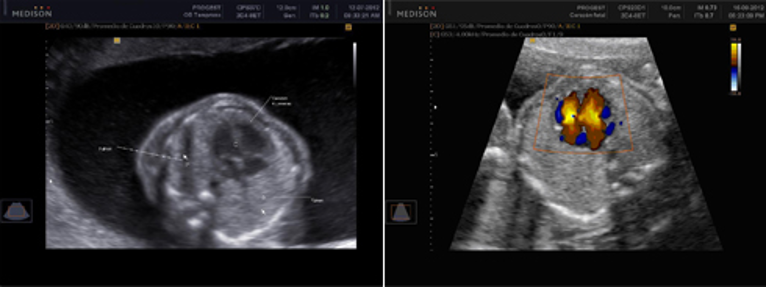

Se realiza por vía abdominal después de la semana 13 y hasta el final de la gestación. Esta ecografía brinda información muy útil sobre la anatomía del bebe, donde se evalúa cada uno de sus órganos, y es de gran utilidad para descartar problemas estructurales o de funcionamiento de algún órgano , formación y crecimiento del bebe, posición de la placenta, cantidad de líquido amniótico, tiempo de gestación, como está la circulación de la placenta y el cordón umbilical, entre otras. A partir de la semana 16 podemos determinar el sexo de tu bebé con una ecografía tradicional en 2D